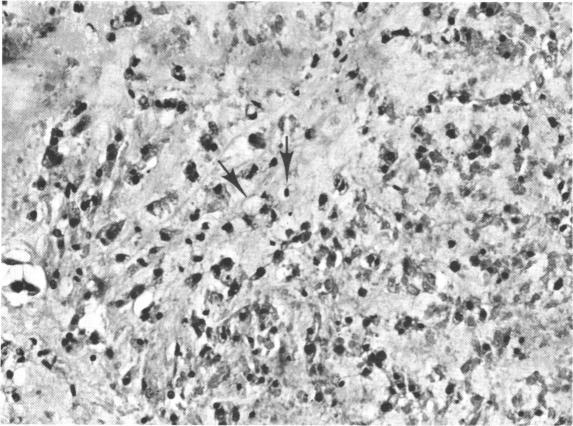

Sixty-three patients with confirmed intracranial chordoma were studied retrospectively to determine the incidence of various presenting symptoms and signs. Most of the ocular signs were due to cranial nerve involvement. Sixth cranial nerve palsy occurred as the sole presenting sign in 29% of patients, whereas extraocular muscle palsies of various combinations were present in 62%. Visual field defects were demonstrated in 24% of patients, but only 19% had papilledema or optic atrophy. The chordomas arose from the clivus in 92% of patients, but different patterns of cranial nerve involvement occurred which correlated with the different sites of extension of the tumor.

对63例确诊为颅内脊索瘤的患者进行了回顾性研究,以确定各种临床表现和体征的发生率。大多数眼部体征是由于脑神经受累所致。29%的患者以第六脑神经麻痹作为唯一的临床表现,而62%的患者存在各种组合的眼外肌麻痹。24%的患者出现视野缺损,但只有19%的患者有视乳头水肿或视神经萎缩。92%的患者脊索瘤起源于斜坡,但出现了不同的脑神经受累模式,这与肿瘤不同的扩展部位相关。